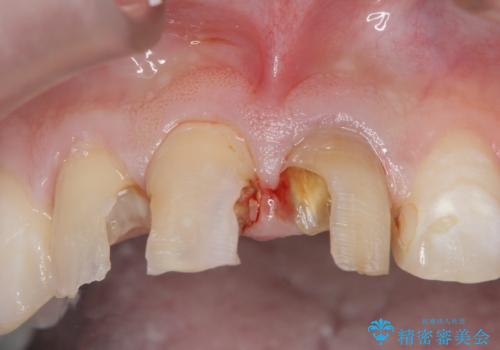

- 前歯の変色や形態を含む、見た目を改善したいと希望され来院されました。

視診・X線検査・歯周組織検査より下記のような問題が列挙され、長期的な予後を見込むために一つづつ問題の解決を計ります。

・不十分な根管治療 →マイクロスコープを用いる精密根管医療

・歯肉縁下カリエス →部分矯正による歯の挺出・歯周外科